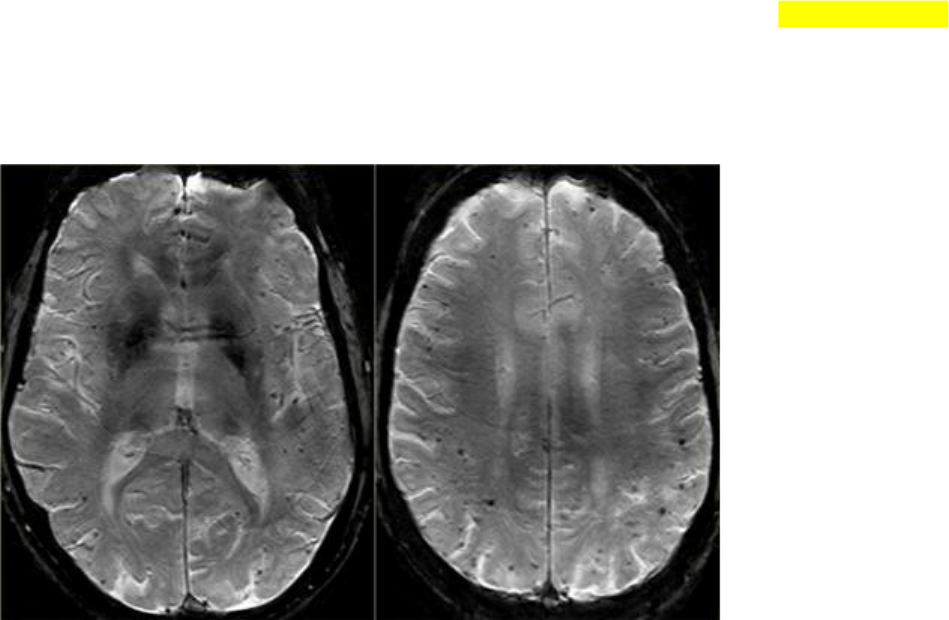

Na RM, a sequência T2 * mostrará múltiplas microhemorragias, tipicamente em uma localização periférica (em oposição às microhemorragias hipertensivas, que geralmente estão localizadas mais centralmente, por exemplo, nos gânglios basais e tálamo).

As imagens T2 * em um paciente com CAA mostram vários microssangues localizados perifericamente.

FLAIR images of the same patient show Fazekas 2 white matter hyprintensities.

T2* images in a patient with CAA microbleeds.